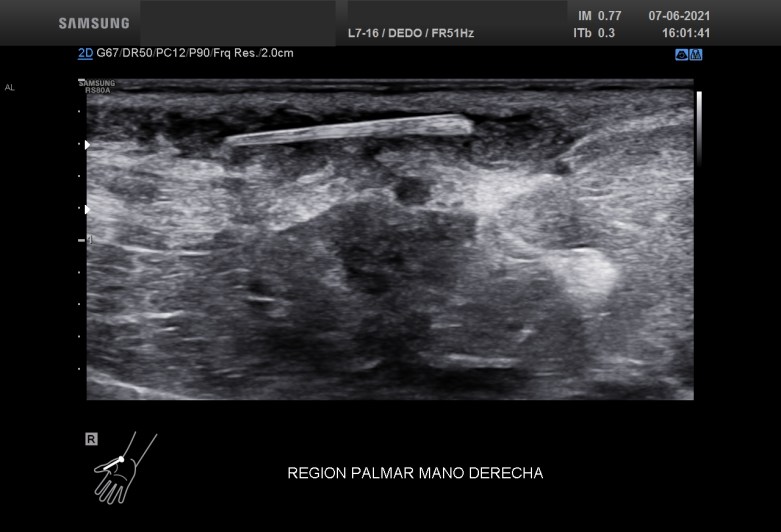

El corte longitudinal o en eje largo la ecoestructura alargada, hiperecogénica se hace claramente con el protagonismo de la imagen, el líquido en este eje parece mayor, y la zona de afectación de esta estructura alojada en el TCS es mucho mayor de lo que parecía en un principio.

En este momento nos hace falta claramente la anatomía, saber perfectamente donde está alojada la ecoestructura o cuerpo extraño que está provocando claramente una reacción a cuerpo extraño. Se demuestra que la situación es subcutánea, no afecta a vasos y no afecta al tejido muscular. En el Tejido Celular Subcutáneo existe claramente cambios en la ecoarquitectura normal de la región, con presencia de líquido y aumento global de las partes blandas del tejido graso. El líquido parece estar floculado, es espeso y además no es anecoico, con lo que podríamos estar delante de algún tipo de infección local que se confirmó tras la extirpación del cuerpo extraño y que precisó tratamiento antibiótico y que queda demostrado en la imagen 3 y la imagen 4.